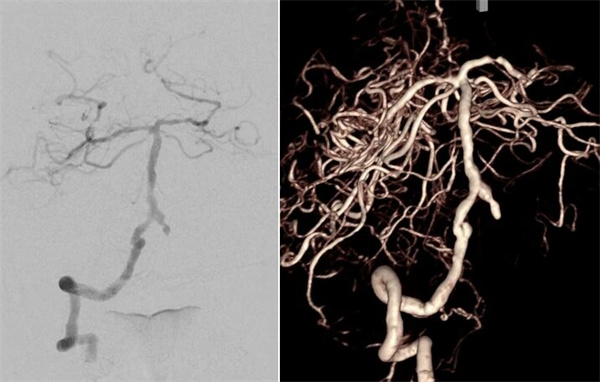

患者高先生,70岁,患有高血压病多年。2年前曾行冠状动脉搭桥术,平素规律服药。2个月前,他因左上肢突然麻木被送至清华大学垂杨柳医院急诊科就诊。头颅CT提示右侧顶叶少量蛛网膜下腔出血。后入住神经外科进一步诊治,全脑血管造影(DSA)结果显示:右侧椎动脉起始部重度狭窄约70%,左侧椎动脉颅内段闭塞;右侧椎动脉颅内段存在大小约3.5×2毫米的夹层动脉瘤;右侧颈内动脉颅外段存在重度狭窄,左侧颈内动脉通过前交通动脉代偿。

▲右侧椎动脉V4段夹层动脉瘤